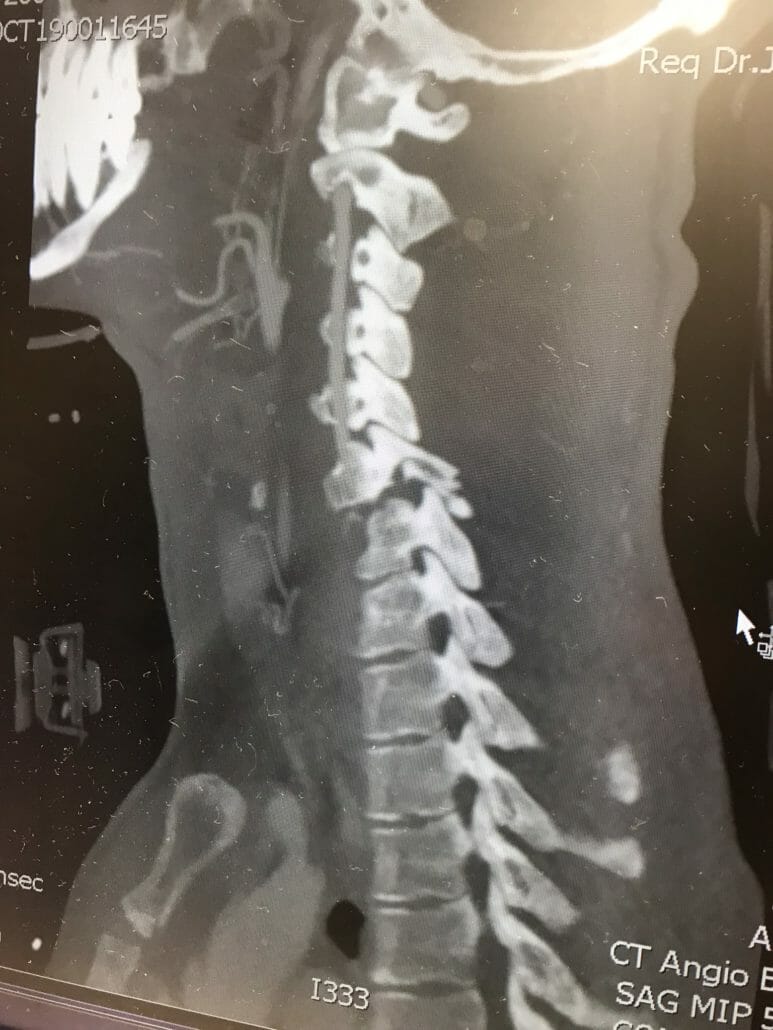

The break is in the area of vertebra C6 and 7. From the chest down he can not move at the moment. The paraplegia is caused by swelling and trauma in the area of the spinal canal. If the swelling goes back, the feeling in the limbs could come back. Whether he can fully recover from the accident is still open.